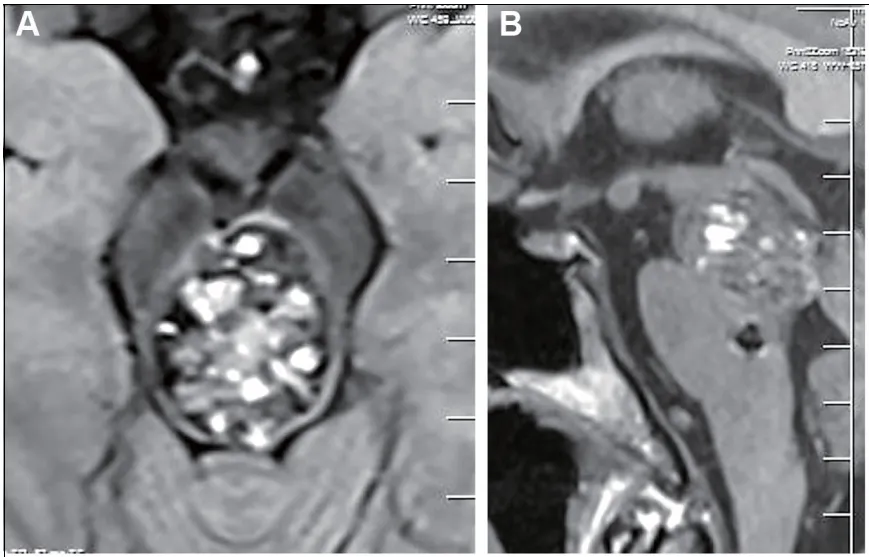

40岁男性患者艾瑞克因复视和行走不稳等临床症状就诊。影像学检查结果显示,患者患有中脑海绵状血管瘤。术前增强磁共振成像清晰显示血管畸形团块存在于轴位和矢状位,同时在脑桥区域检测到直径数毫米的微小卫星病灶。需要特别注意的是,中脑区域虽然仅占全脑体积的0.5%,但作为关键的生命中枢,承担着意识调节、眼球运动控制、视觉和听觉功能调节等重要生理功能,在该区域实施神经外科手术具有较高的风险性。

术前评估显示,患者改良Rankin量表(mRS)评分为1.6分。主要病灶具有明确的出血病史,存在明确的手术指征。治疗团队面临的核心决策难点在于是否需要同期切除卫星病灶。通过综合考量病灶位置深在、神经纤维分布密集、术后出血风险等多重因素,最终决定尊重患者意愿,制定个体化治疗方案:优先切除主病灶,同时保留卫星病灶。手术采用枕下经幕入路,患者取半坐位配合头屈位体位,通过枕部/枕下中线切口,沿着小脑幕边缘进入中脑背侧目标区域。